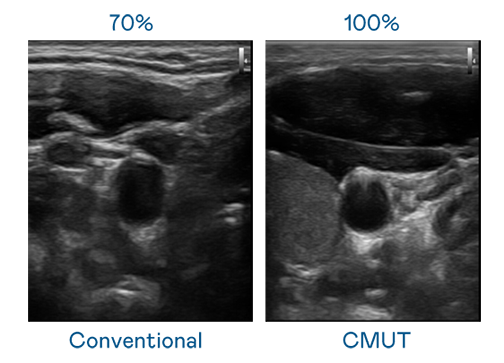

CMUT 技术是一种用电容式微机电元件来产生超音波讯号的技术。与传统 PZT 压电式技术相比,CMUT 频宽增加 30%,更宽频的超音波讯号让影像解析度大幅提升,是实现高影像品质医疗超音波扫描、促进精准医疗发展的关键技术。

超音波影像的解析度高低,首先取决于探头能发出的讯号频宽。金年会jinnianhui官方在线登录 CMUT 可提供高清晰的超音波讯号,提供高频宽、高灵敏度、影像纹理细节更高的超音波影像,协助医护人员缩短影像判读时间及利用精准的医疗影像进行诊断。